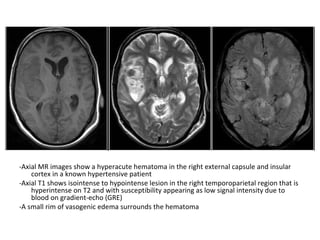

CT and T2W-gradient echo image of a hemorrhagic infarction

limited to the territory of the lateral lenticulostriate arteries